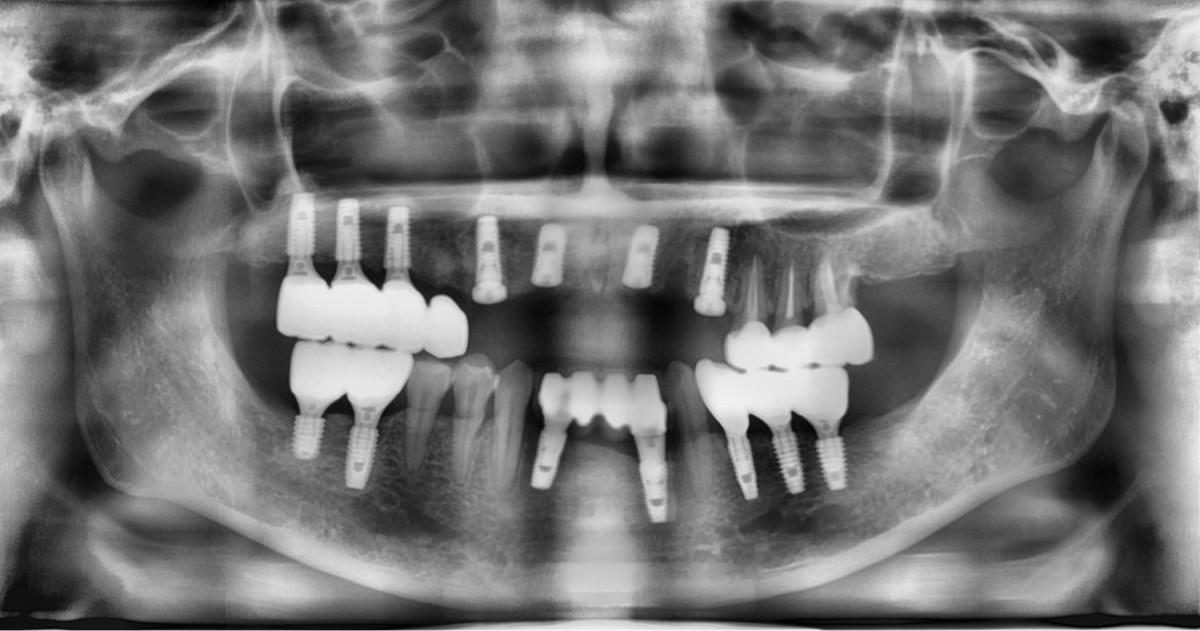

A 46-year-old female patient didn’t

have any systemic problems but a poor oral condition.

The patient is scheduled

for the implant and general prosthetic restoration in various parts. First of

all, the vertical stop is completed by several prostheses in the posterior

region, and the final stage of intraoral restoration is to proceed with an

anterior implant installation.